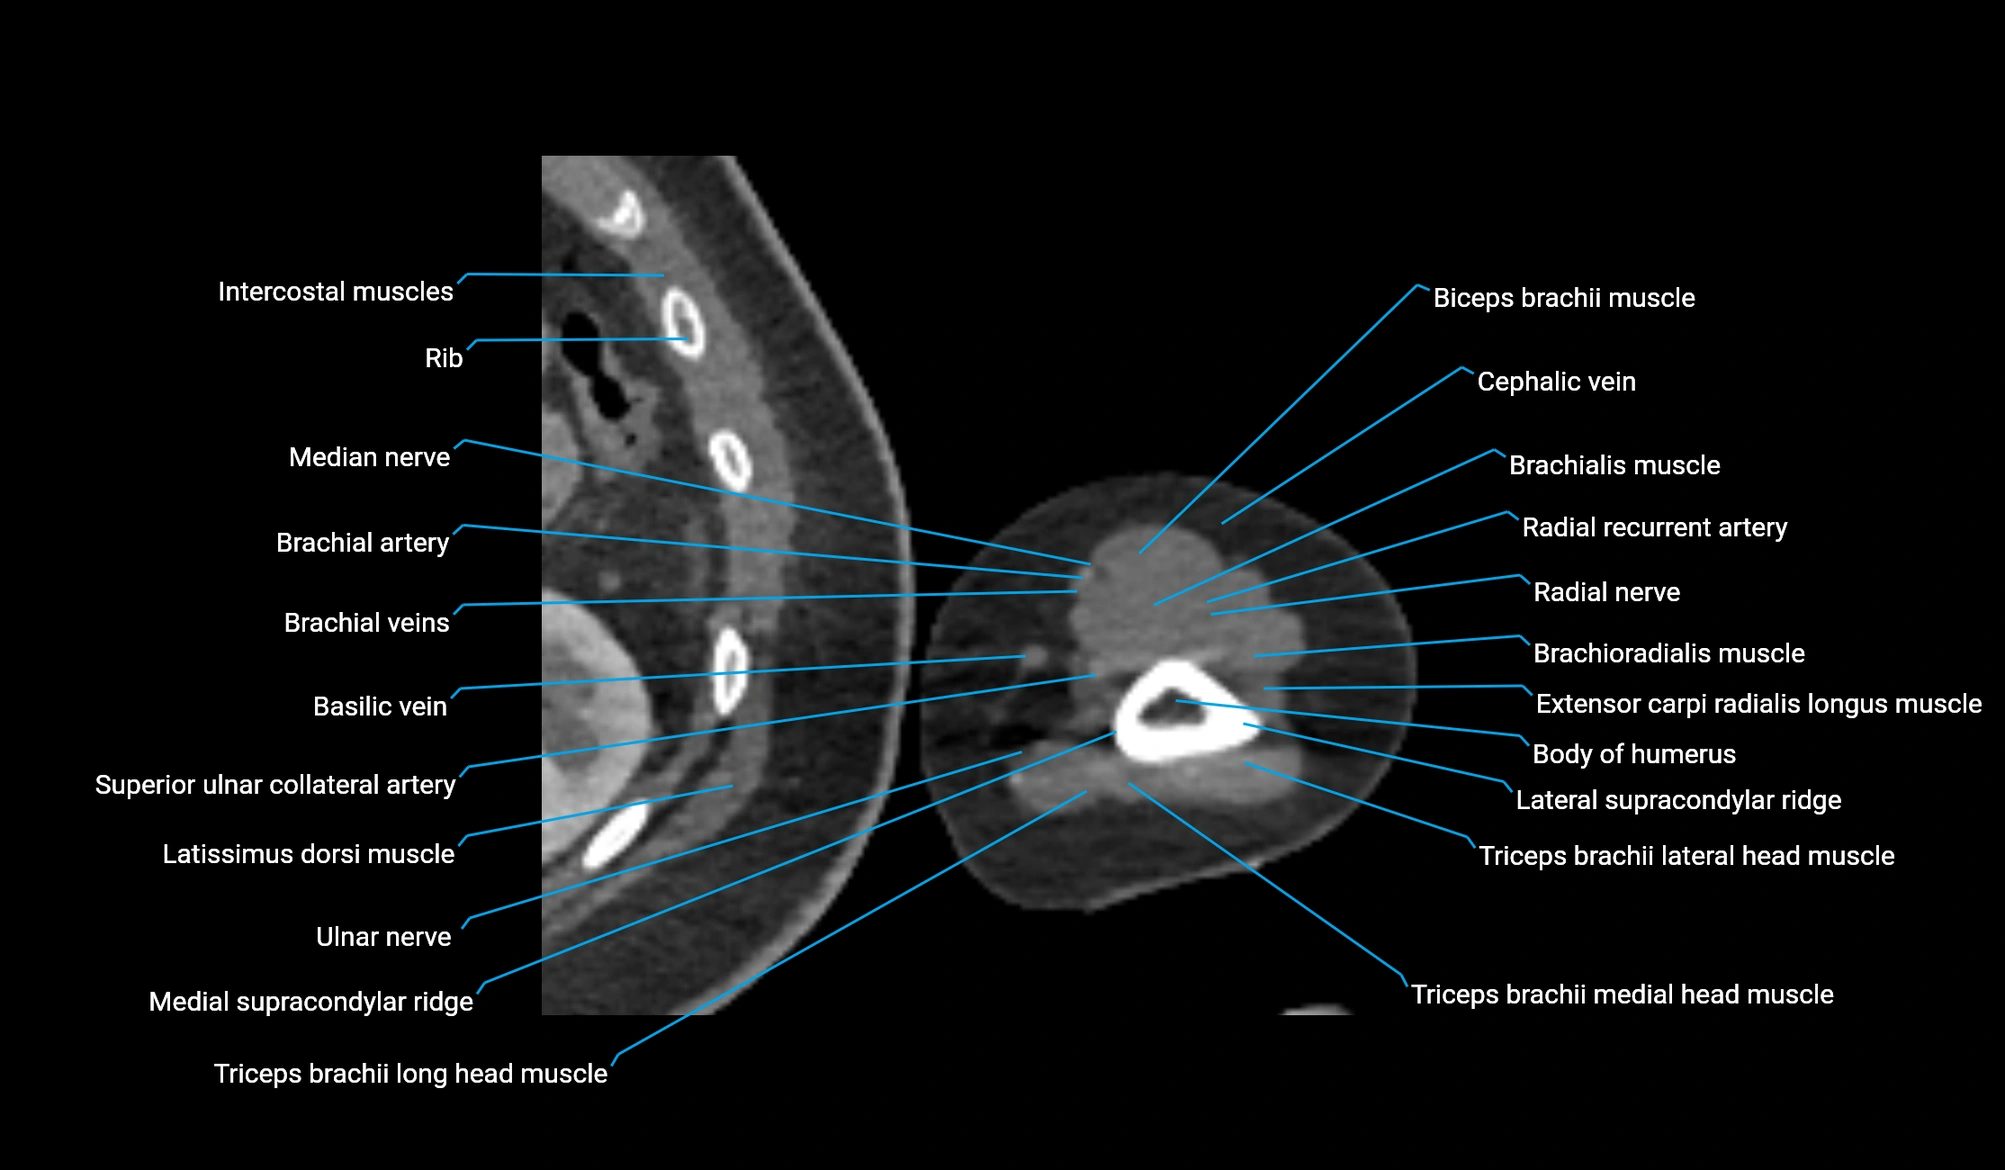

- Body of humerus

- Brachial artery

- Brachialis muscle

- Brachioradialis muscle

- Extensor carpi radialis longus muscle

- Lateral supracondylar ridge

- Long head of triceps brachii muscle

- Lateral head of triceps brachii muscle

- Medial head of triceps brachii muscle

- Medial supracondylar ridge

- Median nerve

- Radial nerve

- Radial recurrent artery

- Superior ulnar collateral artery

- Basilic vein

- Biceps brachii muscle